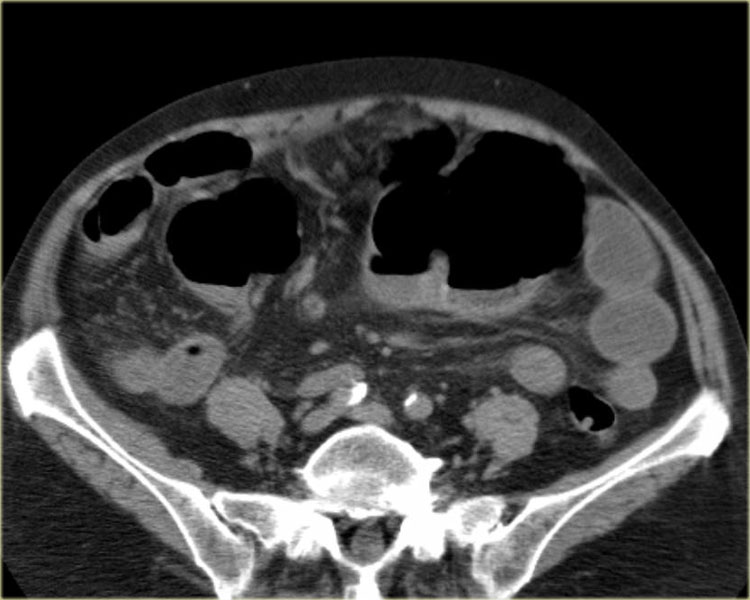

Đây là một bệnh nhân bị tắc ruột non.

Cuộn qua các hình ảnh.

Bạn có thể tìm thấy quai kín và nguyên nhân gây ra nó không?

Khi tiếp nhận bệnh nhân tại phòng cấp cứu với biểu hiện nghi ngờ tắc ruột non (SBO), điều quan trọng nhất chúng ta cần làm, ngoài việc chẩn đoán xác định, là xác định sự hiện diện hay vắng mặt của tình trạng thắt nghẹt.

CT là phương pháp chẩn đoán hình ảnh được lựa chọn trong đánh giá bệnh nhân nghi ngờ tắc ruột non.

Hình ảnh CT của tắc ruột non dạng quai kín phụ thuộc vào hai yếu tố:

- chiều dài đoạn ruột tạo thành quai kín

- hướng của quai ruột so với mặt phẳng tạo ảnh

Nếu quai kín ngắn và nằm trong mặt phẳng tạo ảnh, chúng ta sẽ thấy quai ruột hình chữ U hoặc chữ C.